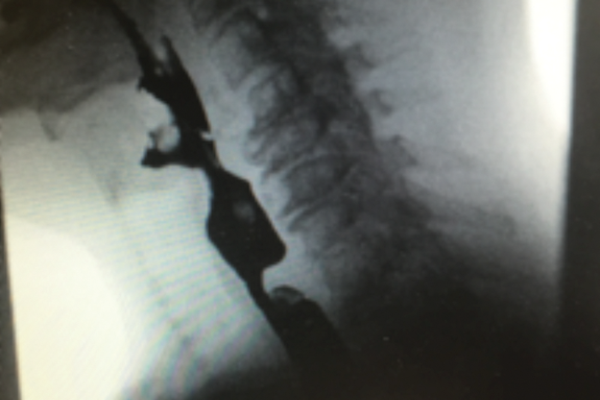

Management of benign oesophageal strictures